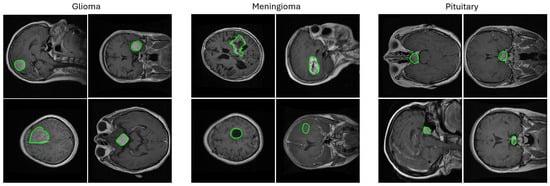

The main categories of brain tumors are glioma, meningioma, and pituitary tumors as shown in Figure 1. Glioma originates in the glial cells and is associated with a higher mortality degree [2]. Low-grade glioma (LGG) and high-grade glioma (HGG) are the two forms of glioma where LGG is less lethal and has generally a better outcome than HGG. Meningioma originates in the meninges—the outer three tissue layers that separate the brain and the skull [9]. Pituitary tumors are abnormal cellular cysts in the pituitary gland, which produces the endocrine hormones. Most pituitary tumors are not cancerous [9].

Figure 1.

Random samples from the 2D T1-weighted CE-MRI dataset [10] used in this study showing images containing three types of brain tumors (meningioma, glioma, and pituitary) in axial, coronal, and sagittal views with ground truth segmentation masks overlaid. The challenges associated with this and other similar brain tumor datasets are the varying tumor sizes, intensities, and textures that range from large bright areas with high contrast surroundings to small dark areas with barely perceivable outlines. The segmentation masks are shown in green contours.